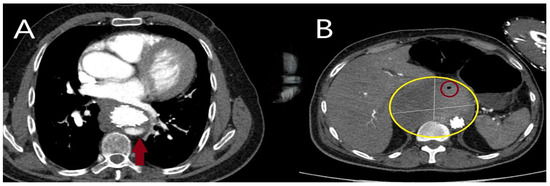

5.2.3. Computed Tomography

5.2.4. Magnetic Resonance Imaging (MRI)